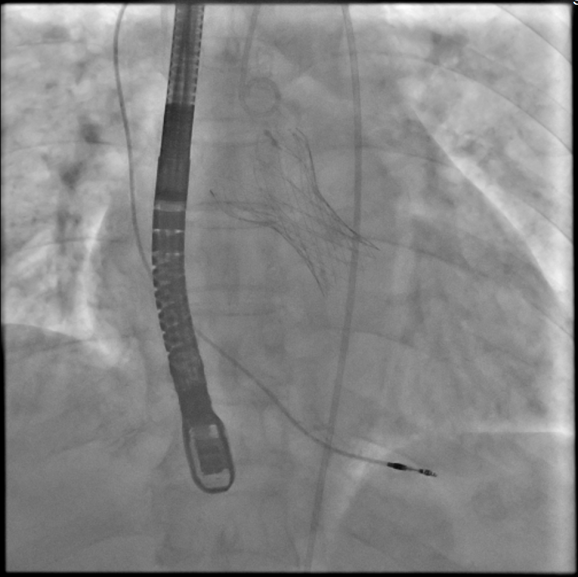

经导管主动脉瓣置换手术术中

患者因“反复活动后胸闷6月”入院,心脏彩超提示存在主动脉瓣二叶畸形合并重度狭窄,最终诊断为主动脉瓣重度狭窄。术前左心室和主动脉压力分别为200mmHg、116mmHg,跨瓣压力84mmHg。术后即刻跨瓣压差小于3mmHg,提示手术效果良好,人工瓣膜位置合适。冠状动脉开口未受影响,术中未见传导阻滞;食道心超提示无瓣周漏,无明显瓣中返流;人工主动脉瓣瓣叶开闭良好、功能正常,二尖瓣开闭不受影响。术后患者胸闷症状明显改善,恢复良好。